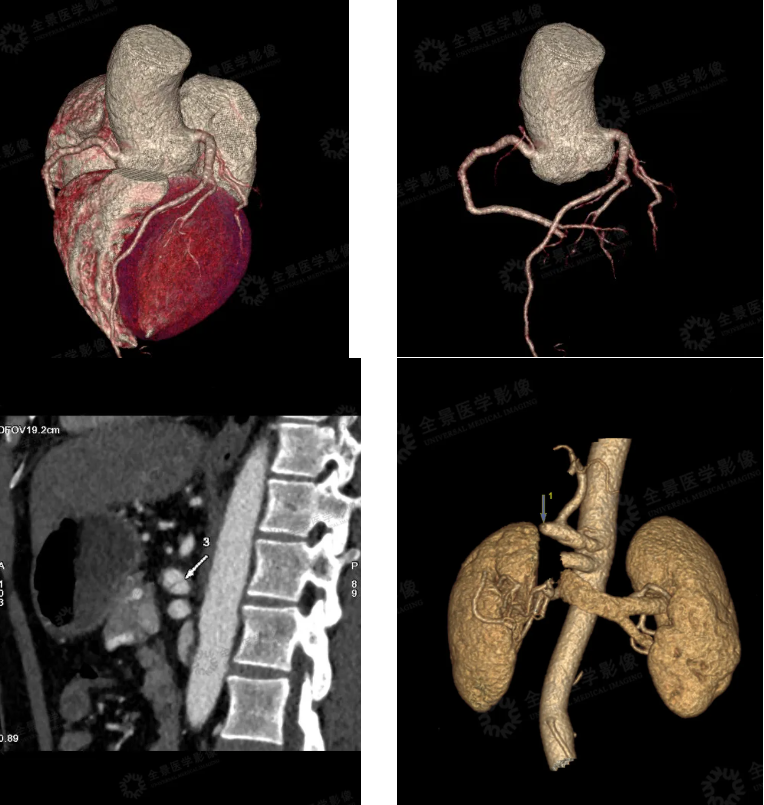

2. 胸腹盆部 CTA 示:腹腔干夹层动脉瘤,远端管壁增厚并软斑形成,管腔重度狭窄,胰腺周围多发侧枝循环形成。(见下图)

付先生体检报告出来后, 全景佲医荟上海博士团医生和影像医生联合为他做了详细报告解读。并告知腹主动脉瘤的诱发生因素和和对健康造成的风险,以及对腹主动脉瘤的进一步治疗建议。

腹主动脉瘤

是腹部主动脉的局部扩张或膨胀,通常是由于动脉壁的薄弱引起的。这种病症在男性中更为常见,尤其是吸烟、高血压、高胆固醇和家族史等风险因素的影响下。许多腹主动脉瘤并没有明显的症状,尤其是在小型瘤体中。但如果瘤体增大,可能会出现:

在家属的诉求中,全景医疗团队通过全程助流程,第一时间对接到重庆某三甲医院血管外科,将检查报告同步医生组织线上会诊,制定治疗方案。医生明确病因为腹主动脉瘤,当天下午就安排住院,血管外科采用微创血管介入治疗,手术也非常顺利。